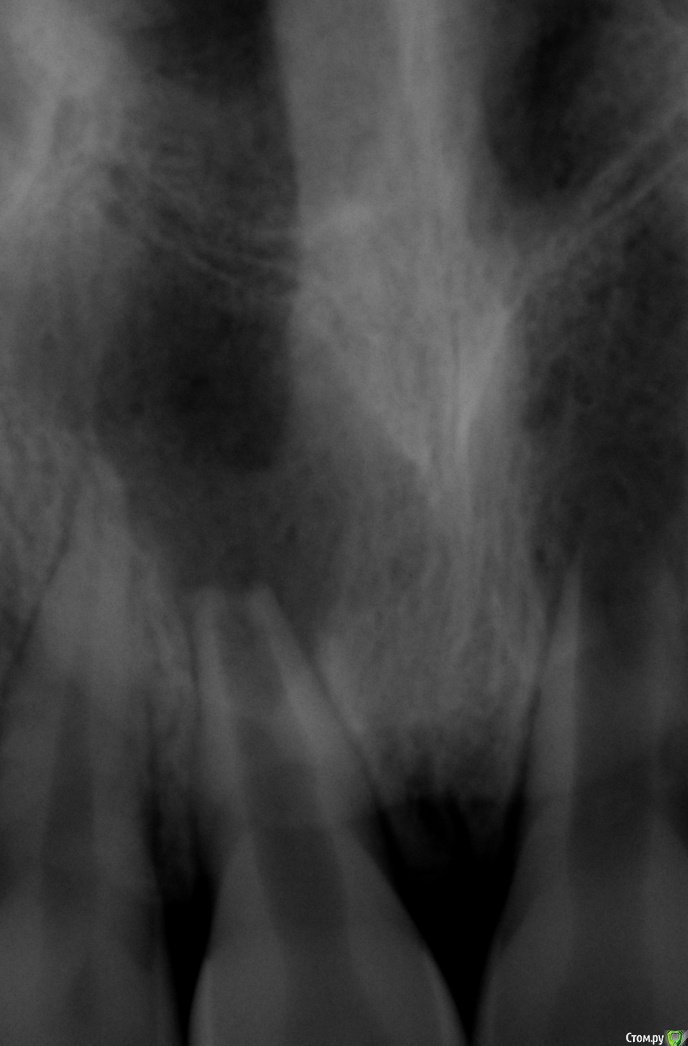

Паращук Роман Опубликовано 12 июня, 2015 Поделиться Опубликовано 12 июня, 2015 Кт,провести эндо с закрытием верхушки мта или ирм. Через 10мес повторное кт для оценки. 4 Ссылка на комментарий

Kainov Опубликовано 12 июня, 2015 Поделиться Опубликовано 12 июня, 2015 Мне кажется, тут ортоградно закрыть нормально не получится. Резцы сдохли давно, мб травма давняя в анамнезе. Предложу ортоградную обработку, затем ретроградно пробки и ортоградно пломбирование оставшейся части канала, возможно даже СИЦем. Ссылка на комментарий

Kainov Опубликовано 12 июня, 2015 Поделиться Опубликовано 12 июня, 2015 А что если это уже все резорбция, все таки зубам 11 лет. И в звязи с чем такое моголо развиться симметрично? Сделайте понораму.Резорбция имеет совершенно другие контуры. Тут налицо остановка дентиногенеза тк пульпа сдохла, как следствие мы видим куски радиолюценции. 2 Ссылка на комментарий

M@estro Опубликовано 12 июня, 2015 Поделиться Опубликовано 12 июня, 2015 Резорбция имеет совершенно другие контуры. Тут налицо остановка дентиногенеза тк пульпа сдохла, как следствие мы видим куски радиолюценции. + 1 , травма лет в 9-10, в период формирования корней . 2 топикстаретер - спросите подробнее пациента, такое не забывают. Имхо - отправить к более опытному специалисту, сами не справитесь. 3 Ссылка на комментарий